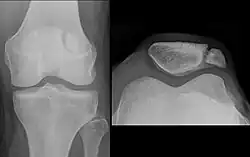

| A fracture of the patella seen on a lateral view | |

The patella can break in various ways depending on the way it is injured, and into two or more pieces.[1] Types include transverse, with one fracture line and is the most common type,[5] marginal, osteochondral and the rare vertical type, or stellate, where a direct compression force gives rise to a comminuted pattern.[5][7] Patella fractures can be further classified as displaced, where the broken ends of bone do not line up correctly and separate by more than 2mm, or undisplaced and stable where pieces of bone remain in contact with each other.[1][7] If fragments of patella bone stick out from the skin it is known as an open patella fracture, and closed if the overlying skin is intact.[1]

Transverse fracture of patella -

Comminuted fracture of patella -

Osteochondral fracture of patella -

Vertical patella fracture